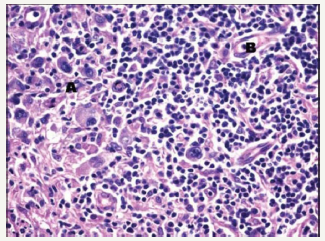

Definitive categories of a Non-Hodgkin’s lymphoma may be witnessed with composite lymphoma. A mantle cell lymphoma and a follicular centre lymphoma defining the constituents of a composite lymphoma, as delineated by the immune histochemical and genetic studies, may elucidate divaricating cellular clones of origin. An immunoglobulin heavy chain (IgH) gene and BCL2 genetic rearrangement may be enunciated within the follicular centre cells. A duplicate clone of tumour cells may be exemplified on immune –histochemistry and genetic assay (Figure 4). Manual or laser capture micro-dissection in conjunction with multiple molecular methodologies for assessing the clone specific neoplasm, particularly the immunoglobulin heavy and light recombinant genetic sequence analysis may be employed [5,6].

Figure 4:CL: nodular sclerosis Hodgkin’s lymphoma with a follicular lymphoma [16].